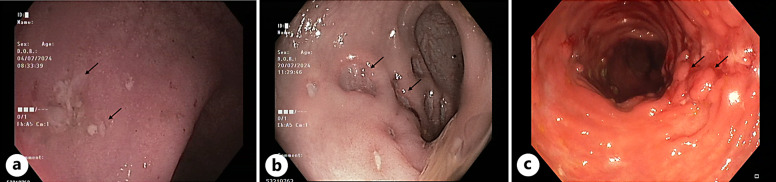

Case presentation: A 69-year-old male with stage IV follicular lymphoma, treated with obinutuzumab-CHOP and subsequent obinutuzumab maintenance therapy, developed non-bloody diarrhea after his third maintenance dose. Endoscopic and histological findings mimicked Crohn's disease, leading to a diagnosis of obinutuzumab-induced pancolitis. Obinutuzumab was discontinued, and the patient was transitioned to infliximab therapy, leading to partial improvement.

Conclusion: This case demonstrates a severe instance of obinutuzumab-induced pancolitis with IBD-like features, emphasizing the need for clinicians to consider drug-induced etiologies in patients presenting with new gastrointestinal symptoms during obinutuzumab therapy. Timely diagnosis and a multidisciplinary approach are crucial for effective management. Further reports are needed to better understand the full spectrum of gastrointestinal toxicity associated with obinutuzumab and guide future treatment.